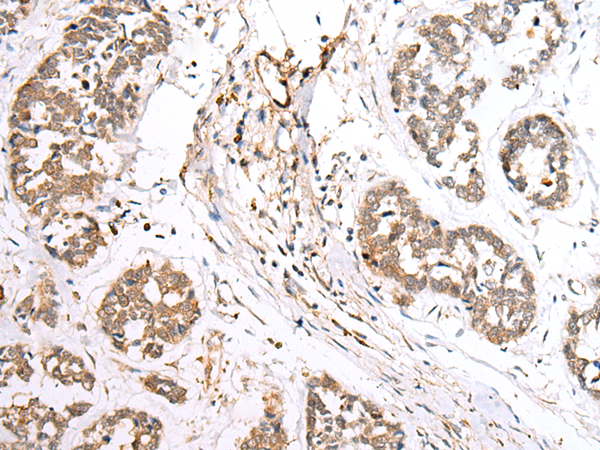

IHC positive control: |

Human tonsil and human esophagus cancer |

IHC Recommend dilution: |

30-150 |